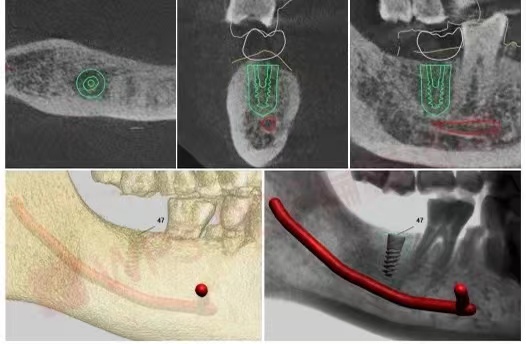

CBCT三维立体全景影像片及术前模拟

这打消了他的担心和疑虑,同时通过直观可视的导板设计界面白叔叔看到了模拟的手术过程及预测的术后效果,让叔叔对手术更有信心。

结合叔叔的骨密度和身体健康状况,在种植体的选择上选定了本次种牙节中的新款德国种植体,具有很强的亲水性,有利于更好的在血液的作用下进行骨结合,同时选择了直径较大的种植体以便于提高种植体的稳定性、缩短骨结合时间。

白叔叔的骨密度情况

安装数字化导板能精准定位种植位置,减小创口和出血,因此杨勇主任要把导板固定在白叔叔口内。杨勇主任在操作过程中在随时关注着白叔叔的状态。

导板种植具有精准、微创、速度快等优点,导板固定地越稳定,种植越准确,误差也就越小,降低术后的肿胀感,让患者的体验感非常好。